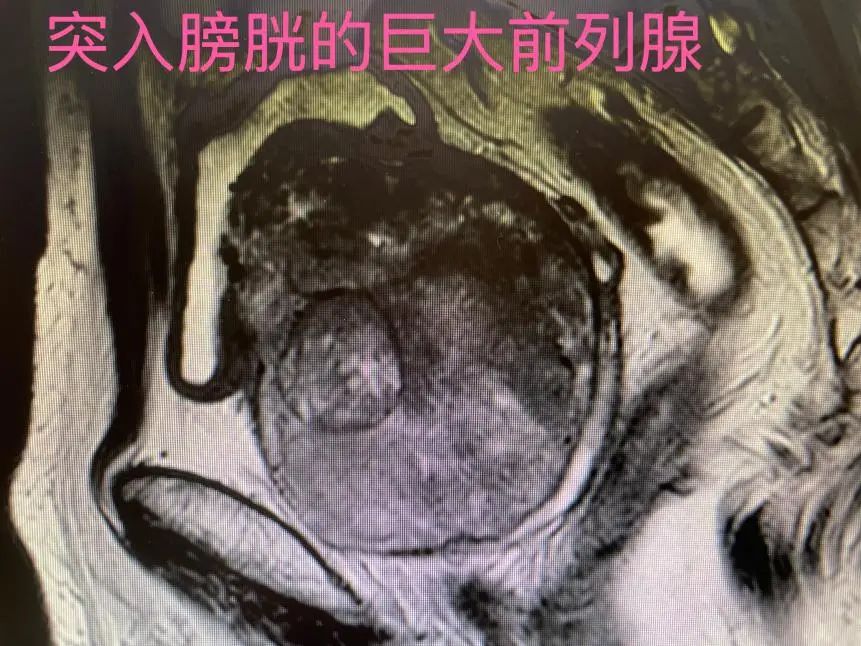

术中发现患者前列腺体积远超预期,中叶严重突入膀胱,导致术野暴露困难。面对挑战,陈主任冷静指挥团队,采用独创的“平均三分法”术式,沿前列腺包膜逆行剜除增生组织,同时利用1470纳米激光的高效汽化特性,在包膜与腺体间精准开辟操作通道。历时90分钟,完整切除重达250克的增生前列腺组织,术中出血量极少,患者生命体征平稳。